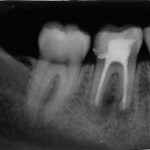

Der Zahn 46 wurde im Frühjahr 2005 während meiner Studentenzeit aufgrund einer irreversiblen Pulpitis nach dem „Goldstandard“ wurzelbehandelt (Kofferdam, mehrfache Einlage mit Ca(OH)2, Spülung mit NaOCl und CHX etc.). Der Zahn wurde anschließend mittels lateraler Kondensation mit Guttapercha und AH-Plus abgefüllt.

Im Juni 2006 stellte sich die Patientin erneut vor. Der Zahn zeigte eine leichte Perkussionsempfindlichkeit und es konnte eine apikale Ostitis im Röntgen dargestellt werden.